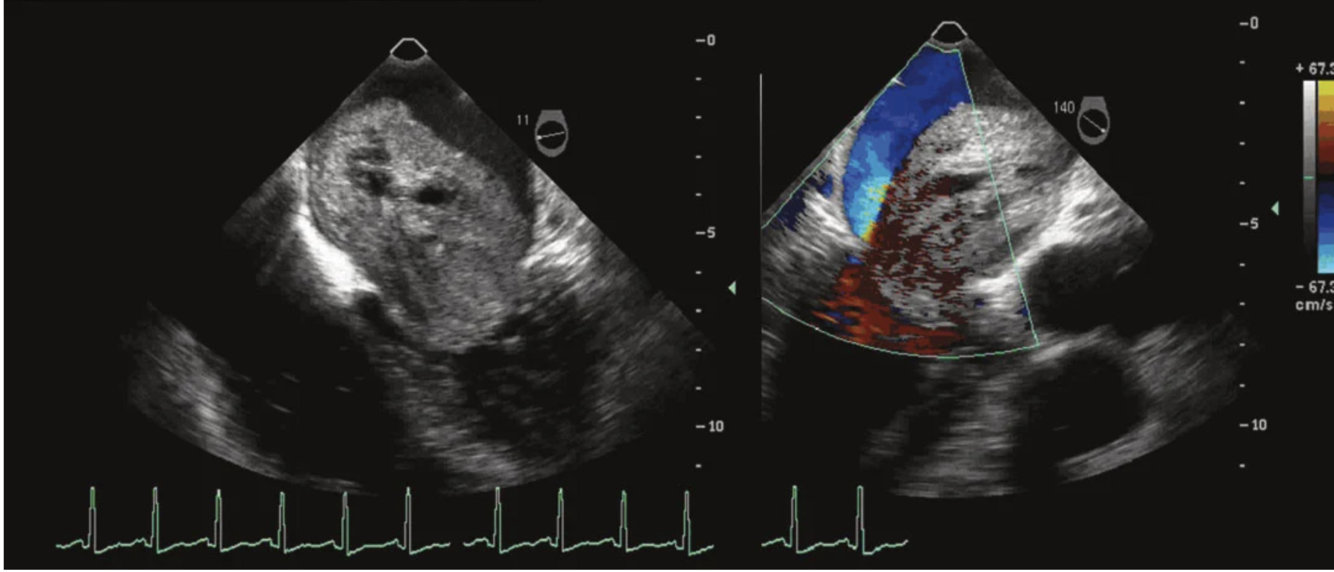

Q

What is the pathology seen in this view?

A

A flail leaflet is diagnosed when ruptured chordae are visualized and the tip of the leaflet points superiorly into the left atrium in systole. In cases of posterior leaflet flail, the regurgitant jet is anteriorly directed.